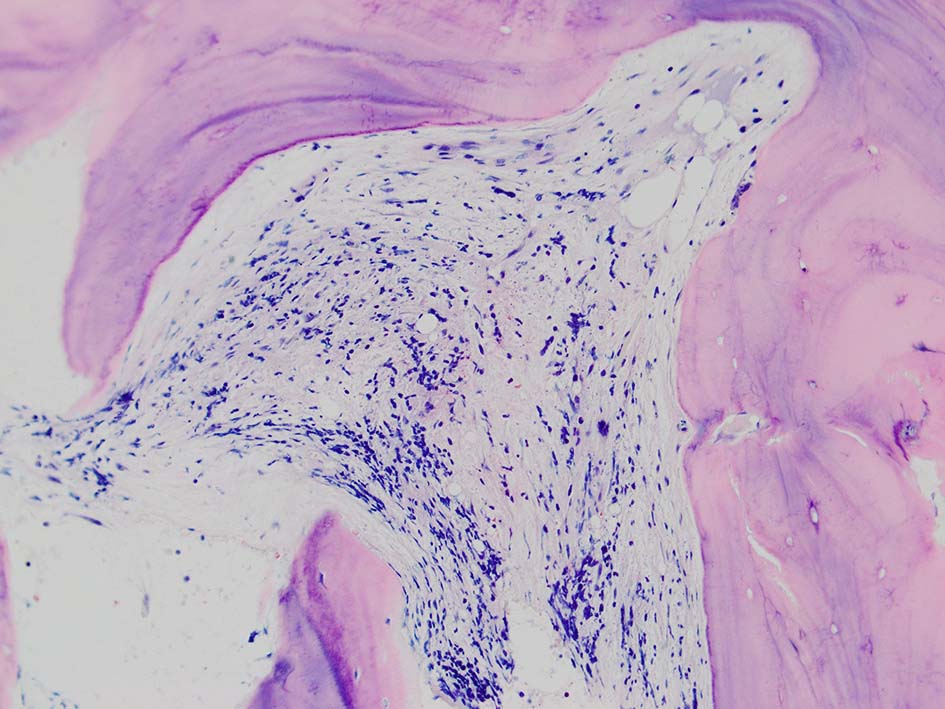

本例ではviableな腫瘍細胞がハーバース管と考えられる管内に認められた.(髄腔とハーバース管腔は解剖学的に同じ場所といえるのか?)

ハーバース管は緻密骨内の骨構造であり, 管内には動静脈, 脈管周囲リンパ管, 神経線維が入る. 解剖学的に海綿骨骨髄腔とは異なる空間構造と考えられる.--viableな腫瘍細胞の存在はリンパ管、血管内への腫瘍浸潤と考えられる.